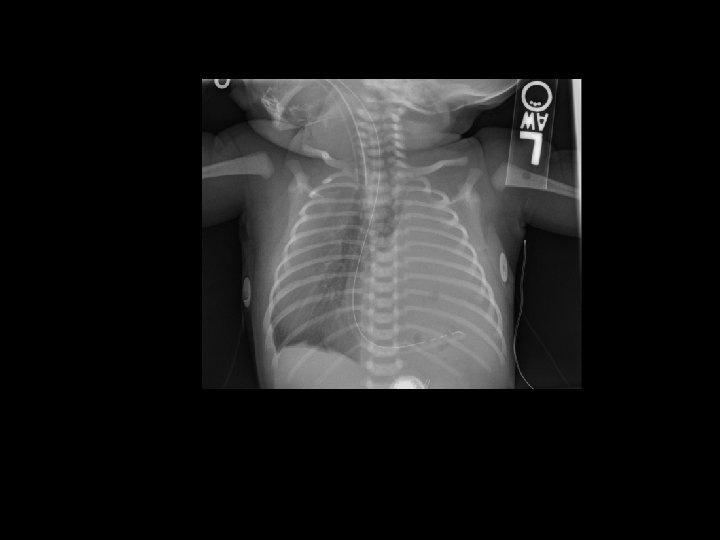

Case 1 Day 12 • On day 12 an Xray was done……

Case 1 Oh, oh…. . • On day 12…. – Free air noted on abdominal XR – No clinical abdominal symptoms • Rx…. – Intubated for transport – NPO – Antibiotic coverage expanded – Transported to Oakland Anna Bergquist CHO MR 960776